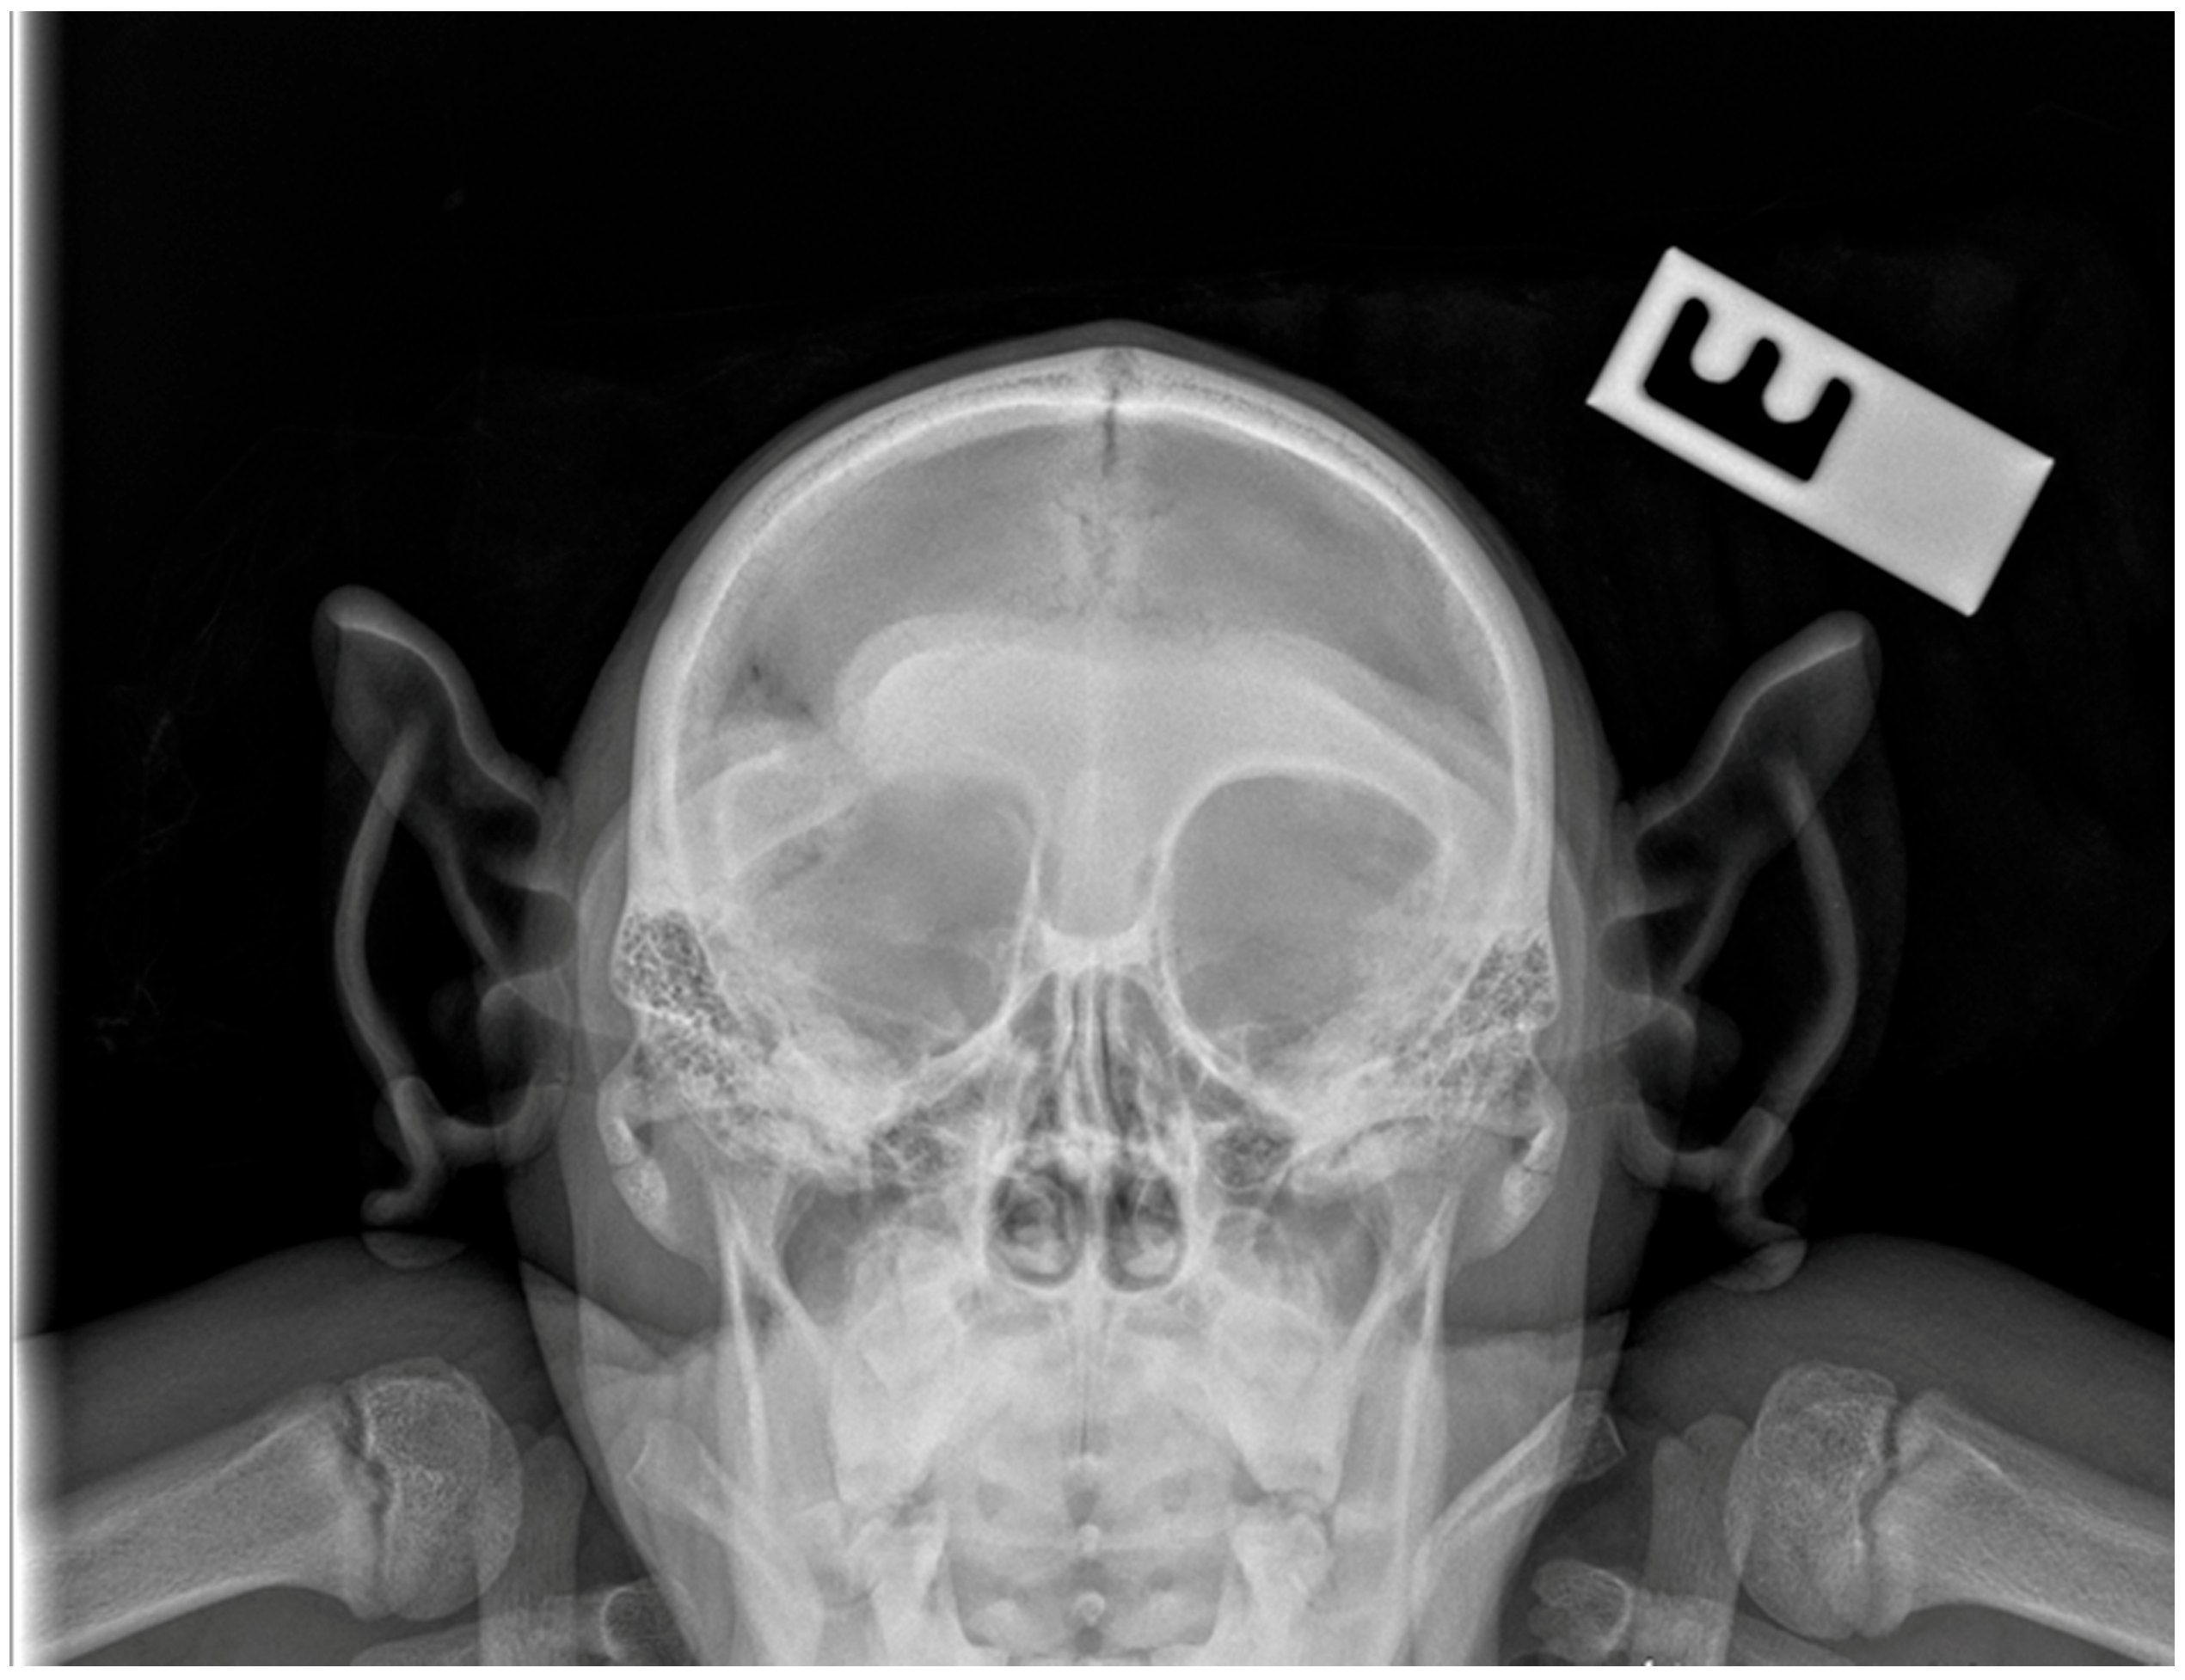

2. Case Presentation

2.2. Surgical Technique